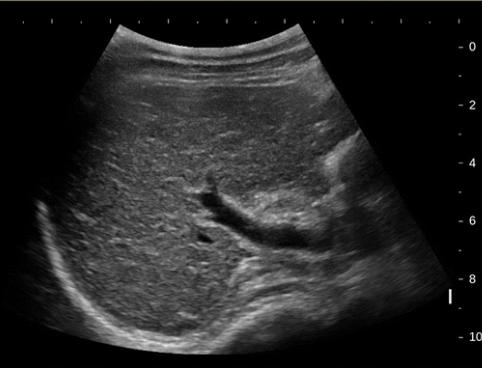

2D US: early stages → hepatomegaly, later/progressive → right ± left lobe atrophy, compensatory caudate lobe hypertrophy, fibrotic heterogenous liver changes, nodular contour, ± hepatic vein compression w/ flattened waveform, PHTN → ascites, splenomegaly, MPV dilation ± reversal of flow

DDX: chronic hepatitis (coarse, fibrotic liver, can turn into cirrhosis if prolonged)